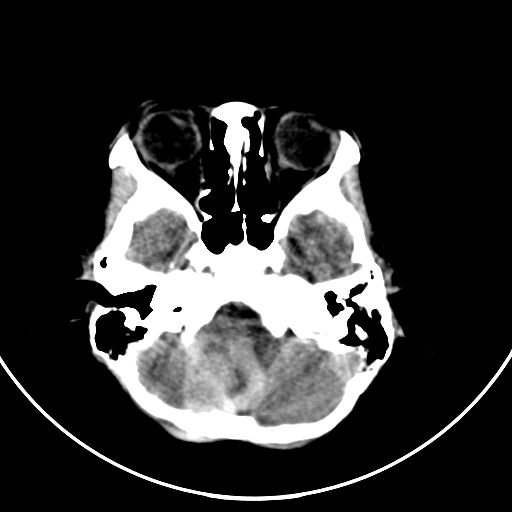

以下是引用zjzjr在2008-7-27 9:56:00的发言:[br]考虑髓母细胞瘤伴梗阻性脑积水.建议增强或mri

以下是引用子十在2008-7-27 9:53:00的发言:[br]考虑髓母细胞瘤